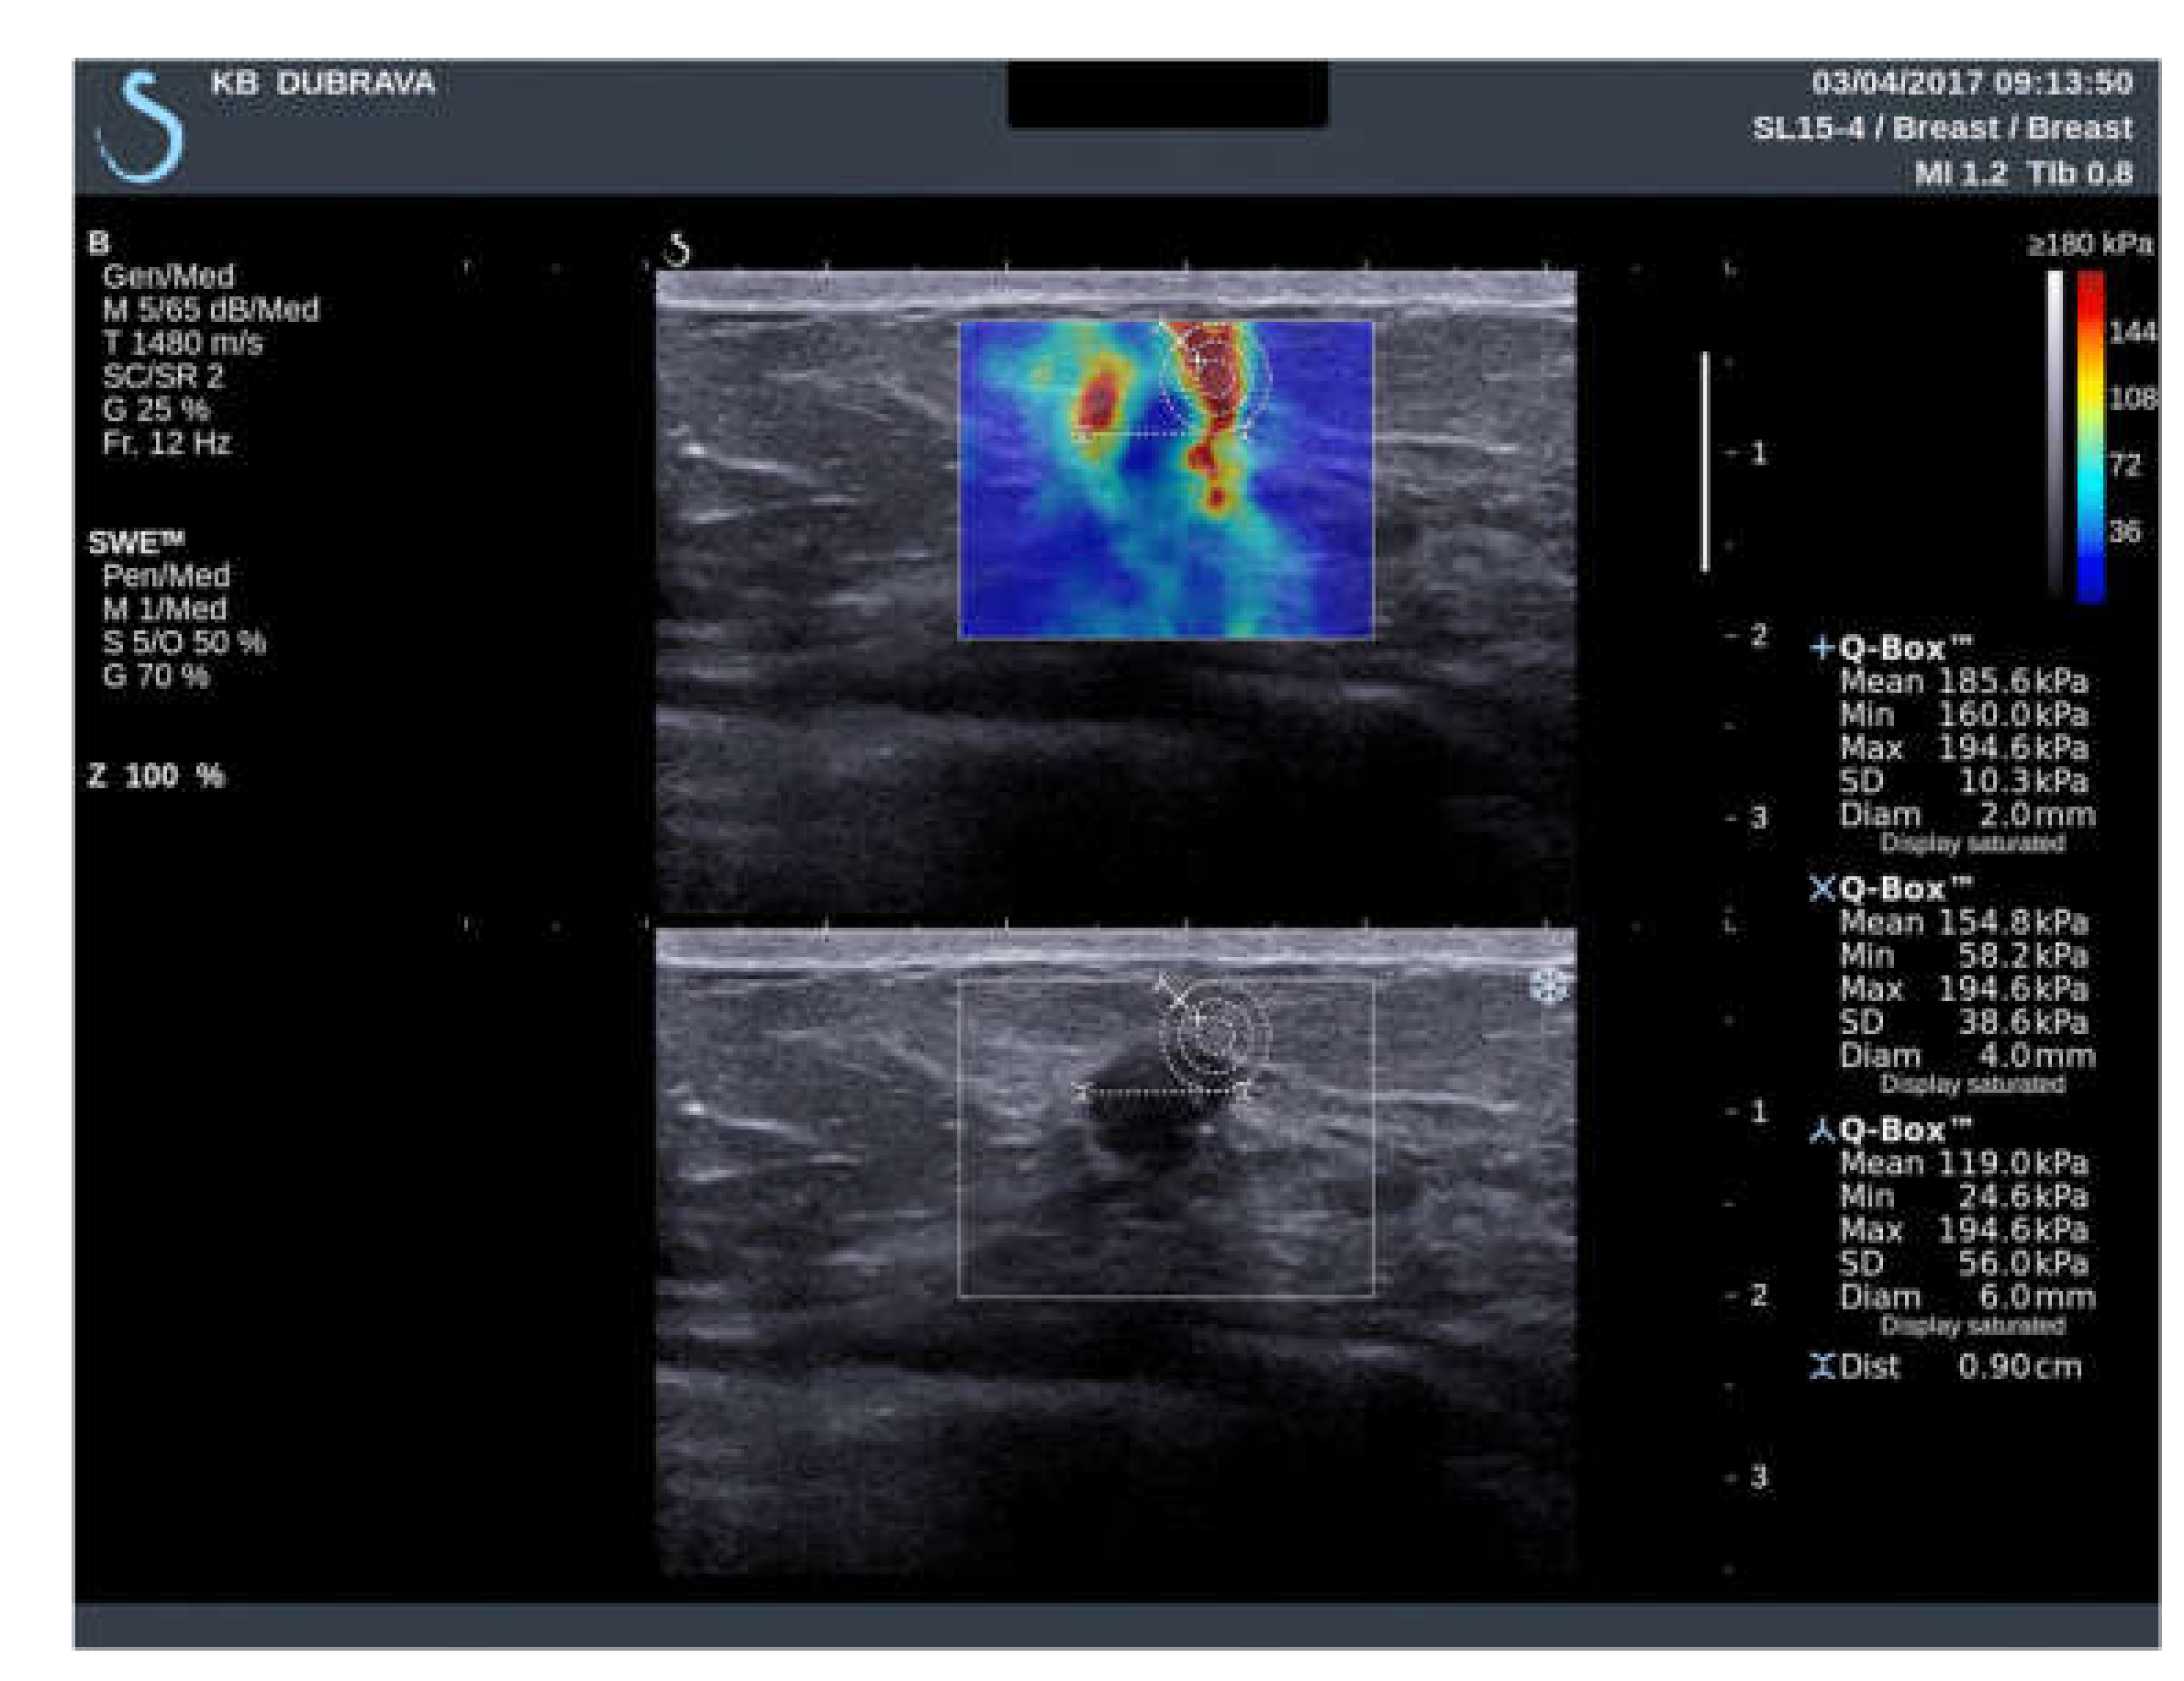

| Variable | ROI 2 mm (1) | ROI 4 mm (2) | ROI 6 mm (3) | p Value |

|---|---|---|---|---|

| Emean (kPa) | 148.85 | 117.55 | 95.65 | <0.001 * (1 vs. 2; 1 vs. 3; 2 vs. 3) * |

| Sd (kPa) | 16.6 | 31.15 | 36.65 | <0.001 * (1 vs. 2; 1 vs. 3; 2 vs. 3) * |

| Coeff. var. (%) | 10.9 | 25.22 | 37.77 | <0.001 * (1 vs. 2; 1 vs. 3; 2 vs. 3) * |

| Emin (kPa) | 108.35 | 50.8 | 23.85 | <0.001 * (1 vs. 2; 1 vs. 3; 2 vs. 3) * |

| Emax (kPa) | 184.45 | 184.45 | 184.45 | 0.236 |

| e-ratio | 8.7 | 6.3 | 3.95 | <0.001 * (1 vs. 2; 1 vs. 3; 2 vs. 3) * |